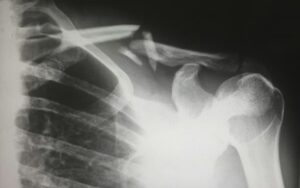

Common Injuries from Motorcycle Accidents in Nevada

Because motorcycles offer little protection in an accident, injuries tend to be severe. Some of the most common injuries include:

- Broken bones and fractures